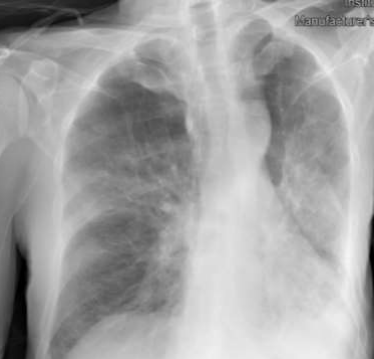

- Did the patient pass away from the lung cancer or from the MUO? He developed cerebral metastasis towards the end of the disease, which is more common in lung cancer compared to MUO. However, MUO generally has a worse prognosis and the CEA was rising. A picture of his X-ray, lung CT and perinephric lesion on CT before death are provided below. You can clearly see that the lung tumour was not locally progressing. It is more likely that he passed away from the MUO. Also, you can see that towards the end of the disease, he developed suspicious subcutaneous soft tissue nodules in the right gluteal region, uncommon to lung cancer .

Fig 9: Xray before death

Fig 10: CT chest before death